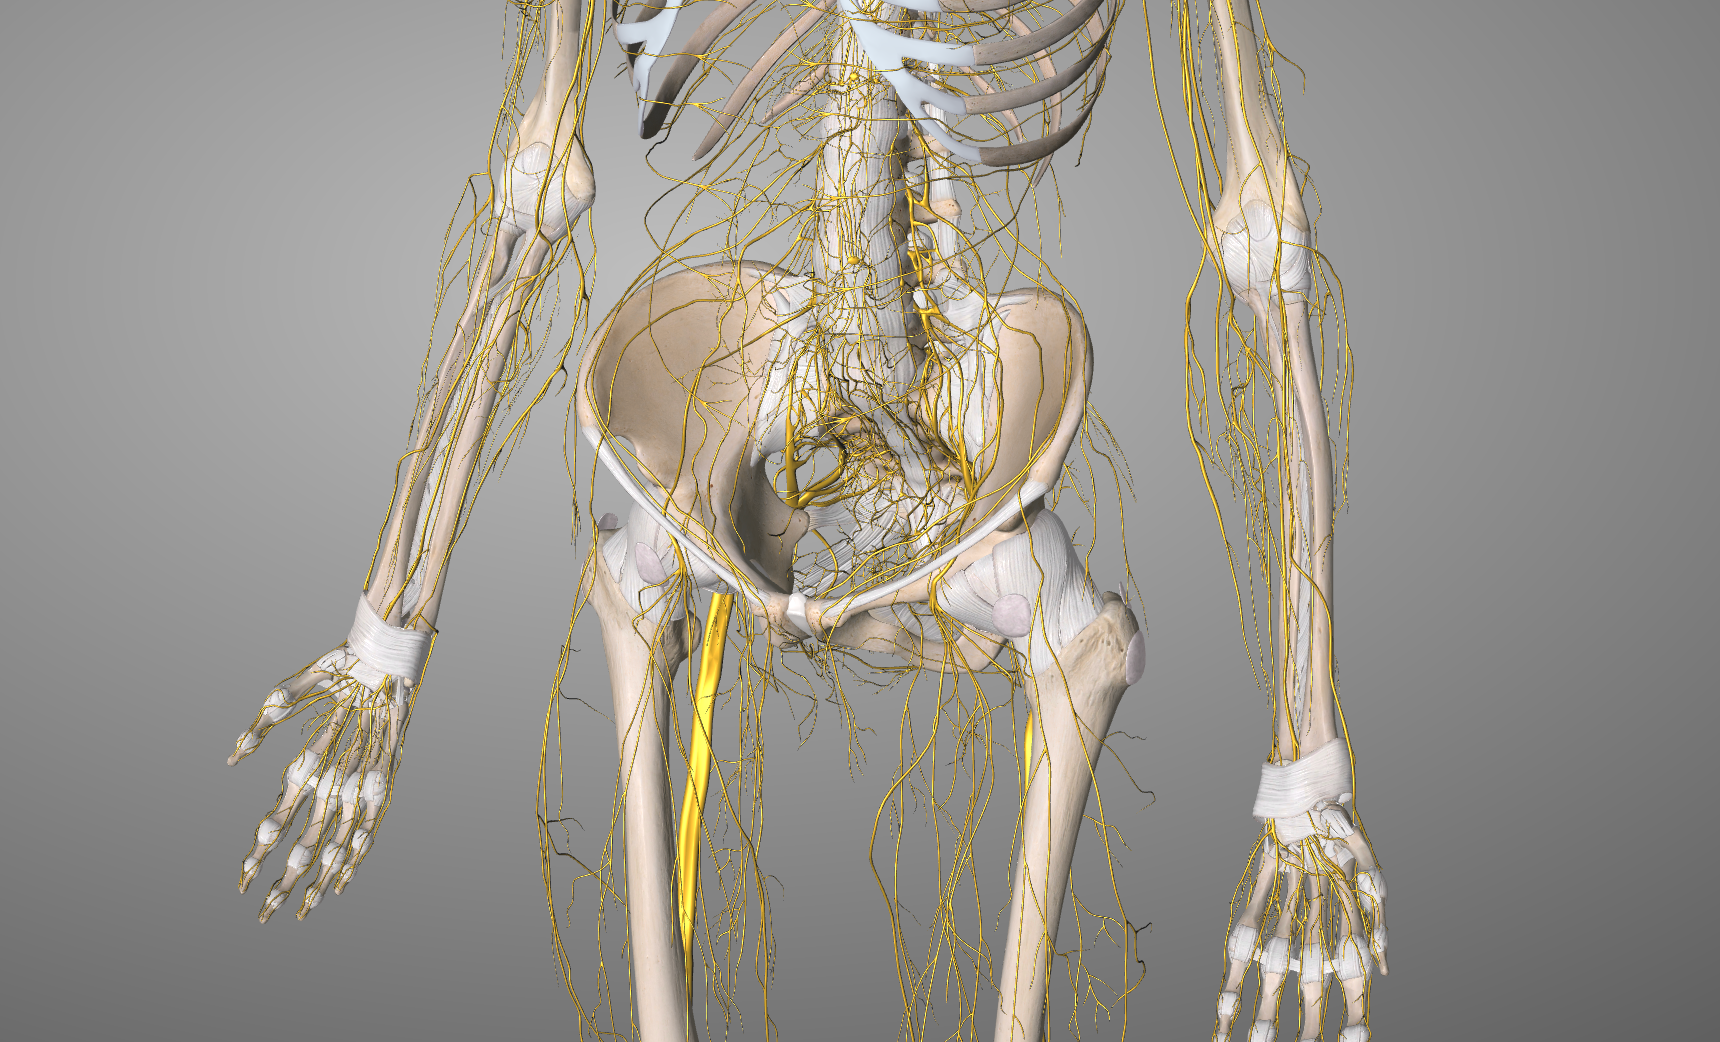

NEURODINÁMICA, la técnica para movilizar el sistema nervioso

NEURODINÁMICA, la técnica utilizada para movilizar el Sistema Nervioso

QUÉ ES LA NEURODINÁMICA:

La

técnica de neurodinámica se utiliza en fisioterapia para evaluar y tratar disfunciones del sistema nervioso periférico que afectan a su

movilidad, sensibilidad y función. Su objetivo es mejorar el

deslizamiento, la elasticidad y la capacidad de adaptación de los nervios dentro de sus interfases anatómicas.

La NEURODINÁMICA como tratamiento, es una técnica que nos ayuda, por lo tanto, a movilizar o poner en tensión el sistema nervioso a través de lo que denominamos su interfase. El término interfase se refiere a las estructuras anatómicas que rodean, soportan y guían el recorrido de un nervio, influyendo en su movilidad y función.

EL CUERPO HUMANO COMO MODELO DE TENSEGRIDAD

Se considera un sistema de tensegridad si dicho sistema se encuentra en un estado de autoequilibrio estable, formado por elementos que soportan compresión y elementos que soportan tracción

Se considera que los huesos son componentes de compresión discontinuos que se encuentran “flotando” en un tejido de tensión continua de las partes blandas, por lo tanto podemos interpretar el cuerpo humano desde la perspectiva de un SISTEMA DE TENSEGRIDAD.

Dicho de otro modo, el concepto de tensegridad describe cómo el cuerpo humano mantiene su estructura y función a través de una distribución equilibrada de tensiones y compresiones. En el sistema musculoesquelético, los músculos, fascias y el resto de tejidos blandos pueden generar tensión, mientras que los huesos actúan como elementos compresivos pudiendo soportar la compresión de las cargas. Esta interacción permite la estabilidad dinámica o en movimiento y la adaptación del cuerpo a las fuerzas externas.

NEURODINÁMICA Y SU RELACIÓN CON LA TENSEGRIDAD

Los nervios están integrados dentro del sistema fascial y su movilidad depende de la continuidad mecánica de todo el sistema de tensegridad. Esto implica que: